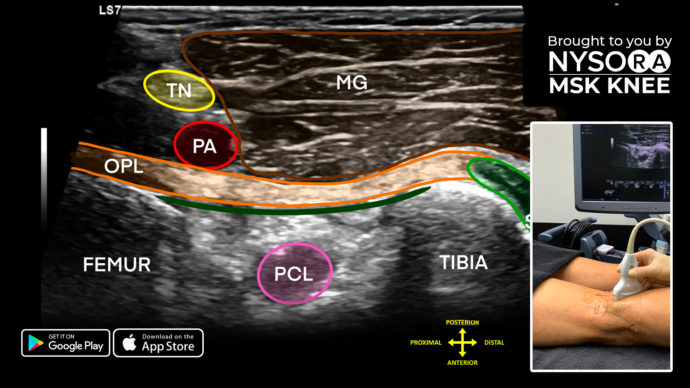

34. Knee Injections